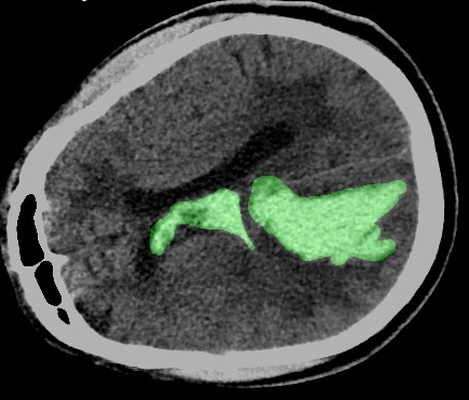

ICH Detection, Classification, Segmentation

The project focused on classifying, detecting, and segmenting hemorrhagic lesions in CT scans using a novel multi-step approach. We developed a multi-step method primarily aimed at increasing the performance of the segmentation process for 3D medical images. The approach includes the development of a novel post-processing method to refine segmentation outcomes, as well as a trainable pre-processing technique to enhance input data quality before model training. Ongoing research explores models like Vision Transformers (ViTs) and sequential models such as RNN and GRU within this framework. To enhance interpretability and explainability for medical specialists, we are developing a decision policy based on fuzzy systems. We also conducted a comprehensive statistical review of the datasets to uncover meaningful patterns within the available data. A key achievement was the creation of a custom dataset of over 900 patient CT scans for segmentation and quantification of intracerebral hemorrhage volume, in collaboration with Iran Medical University and Rasool Akram Hospital. Explainability tools like GradCAM were integrated to improve model transparency, followed by t-SNE transformations to visualize high-dimensional data and model behavior more effectively. This project was my bachelor thesis, resulting in one published paper and another currently in progress. I served as the technical manager of research and development for this project at APAC group.